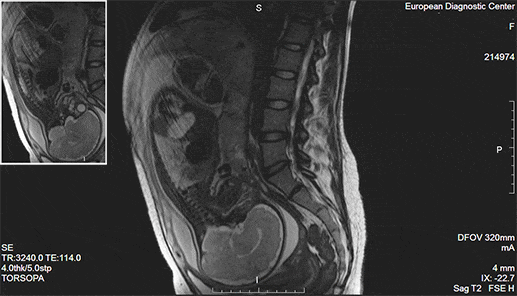

Магнитно-резонансная томография (МРТ)

Магнитно-резонансная томография появилась почти одновременно с компьютерной: в 70-х годах 20 века. Как и КТ, МРТ отображает четкие срезы нужных органов в разных плоскостях в виде контрастных черно-белых картинок и делает возможным получение 3D модели органов. По информативности и точности магнитно-резонансная томография не уступает (и где-то даже превосходит) КТ. По безопасности метод затмевает рентгенодиагностику, так как «не облучает пациентов».

Томограф представляет собой большой магнит определенной мощности. Изображения органов и тканей он строит, оценивая скорость их реакции на электромагнитные волны, которые он излучает. Чаще всего в клинической практике встречаются 1.5 Тл томографы, в большинстве случаев они дают исчерпывающую информацию о структуре тканей и органов. Показания к МРТ обширны. Это и заболевания внутренних органов, и сосудистые нарушения, и опухоли. Но явные преимущества магнитно-резонансная томография имеет при изучении патологий суставов, диагностике заболеваний головного мозга, спинного мозга, органов малого таза.

-10

МРТ определенно перехватил бы пальму первенства у КТ и рентгена, если бы не одно серьезное «но» – исследование проводится в закрытом пространстве и длится больше часа. По этой причине оно не подойдет тяжелым пациентам, людям с клаустрофобией и психическими расстройствами. Процедуру нельзя проводить и тем, у кого есть электронные и металлические конструкции в теле, – электромагнитные волны могут нарушить их работу и положение.